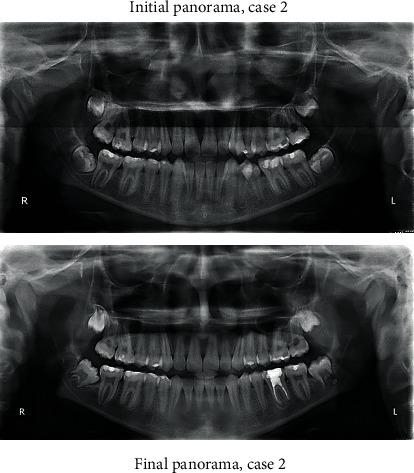

Distalization is a conservative method that is utilized in orthodontics to gain space by moving posterior teeth distally. It may be combined with other space gaining strategies, such as expansion, or can be used alone. Many methods have been used for distalization. These methods differ significantly in their place, whether to be extraoral or intraoral, site of action in upper and/or lower arch, and cooperation needed by the patient if it is removable or fixed. This review illustrates some of the most commonly used methods for distalization with a brief presentation of three cases that incorporated successful distalization techniques.